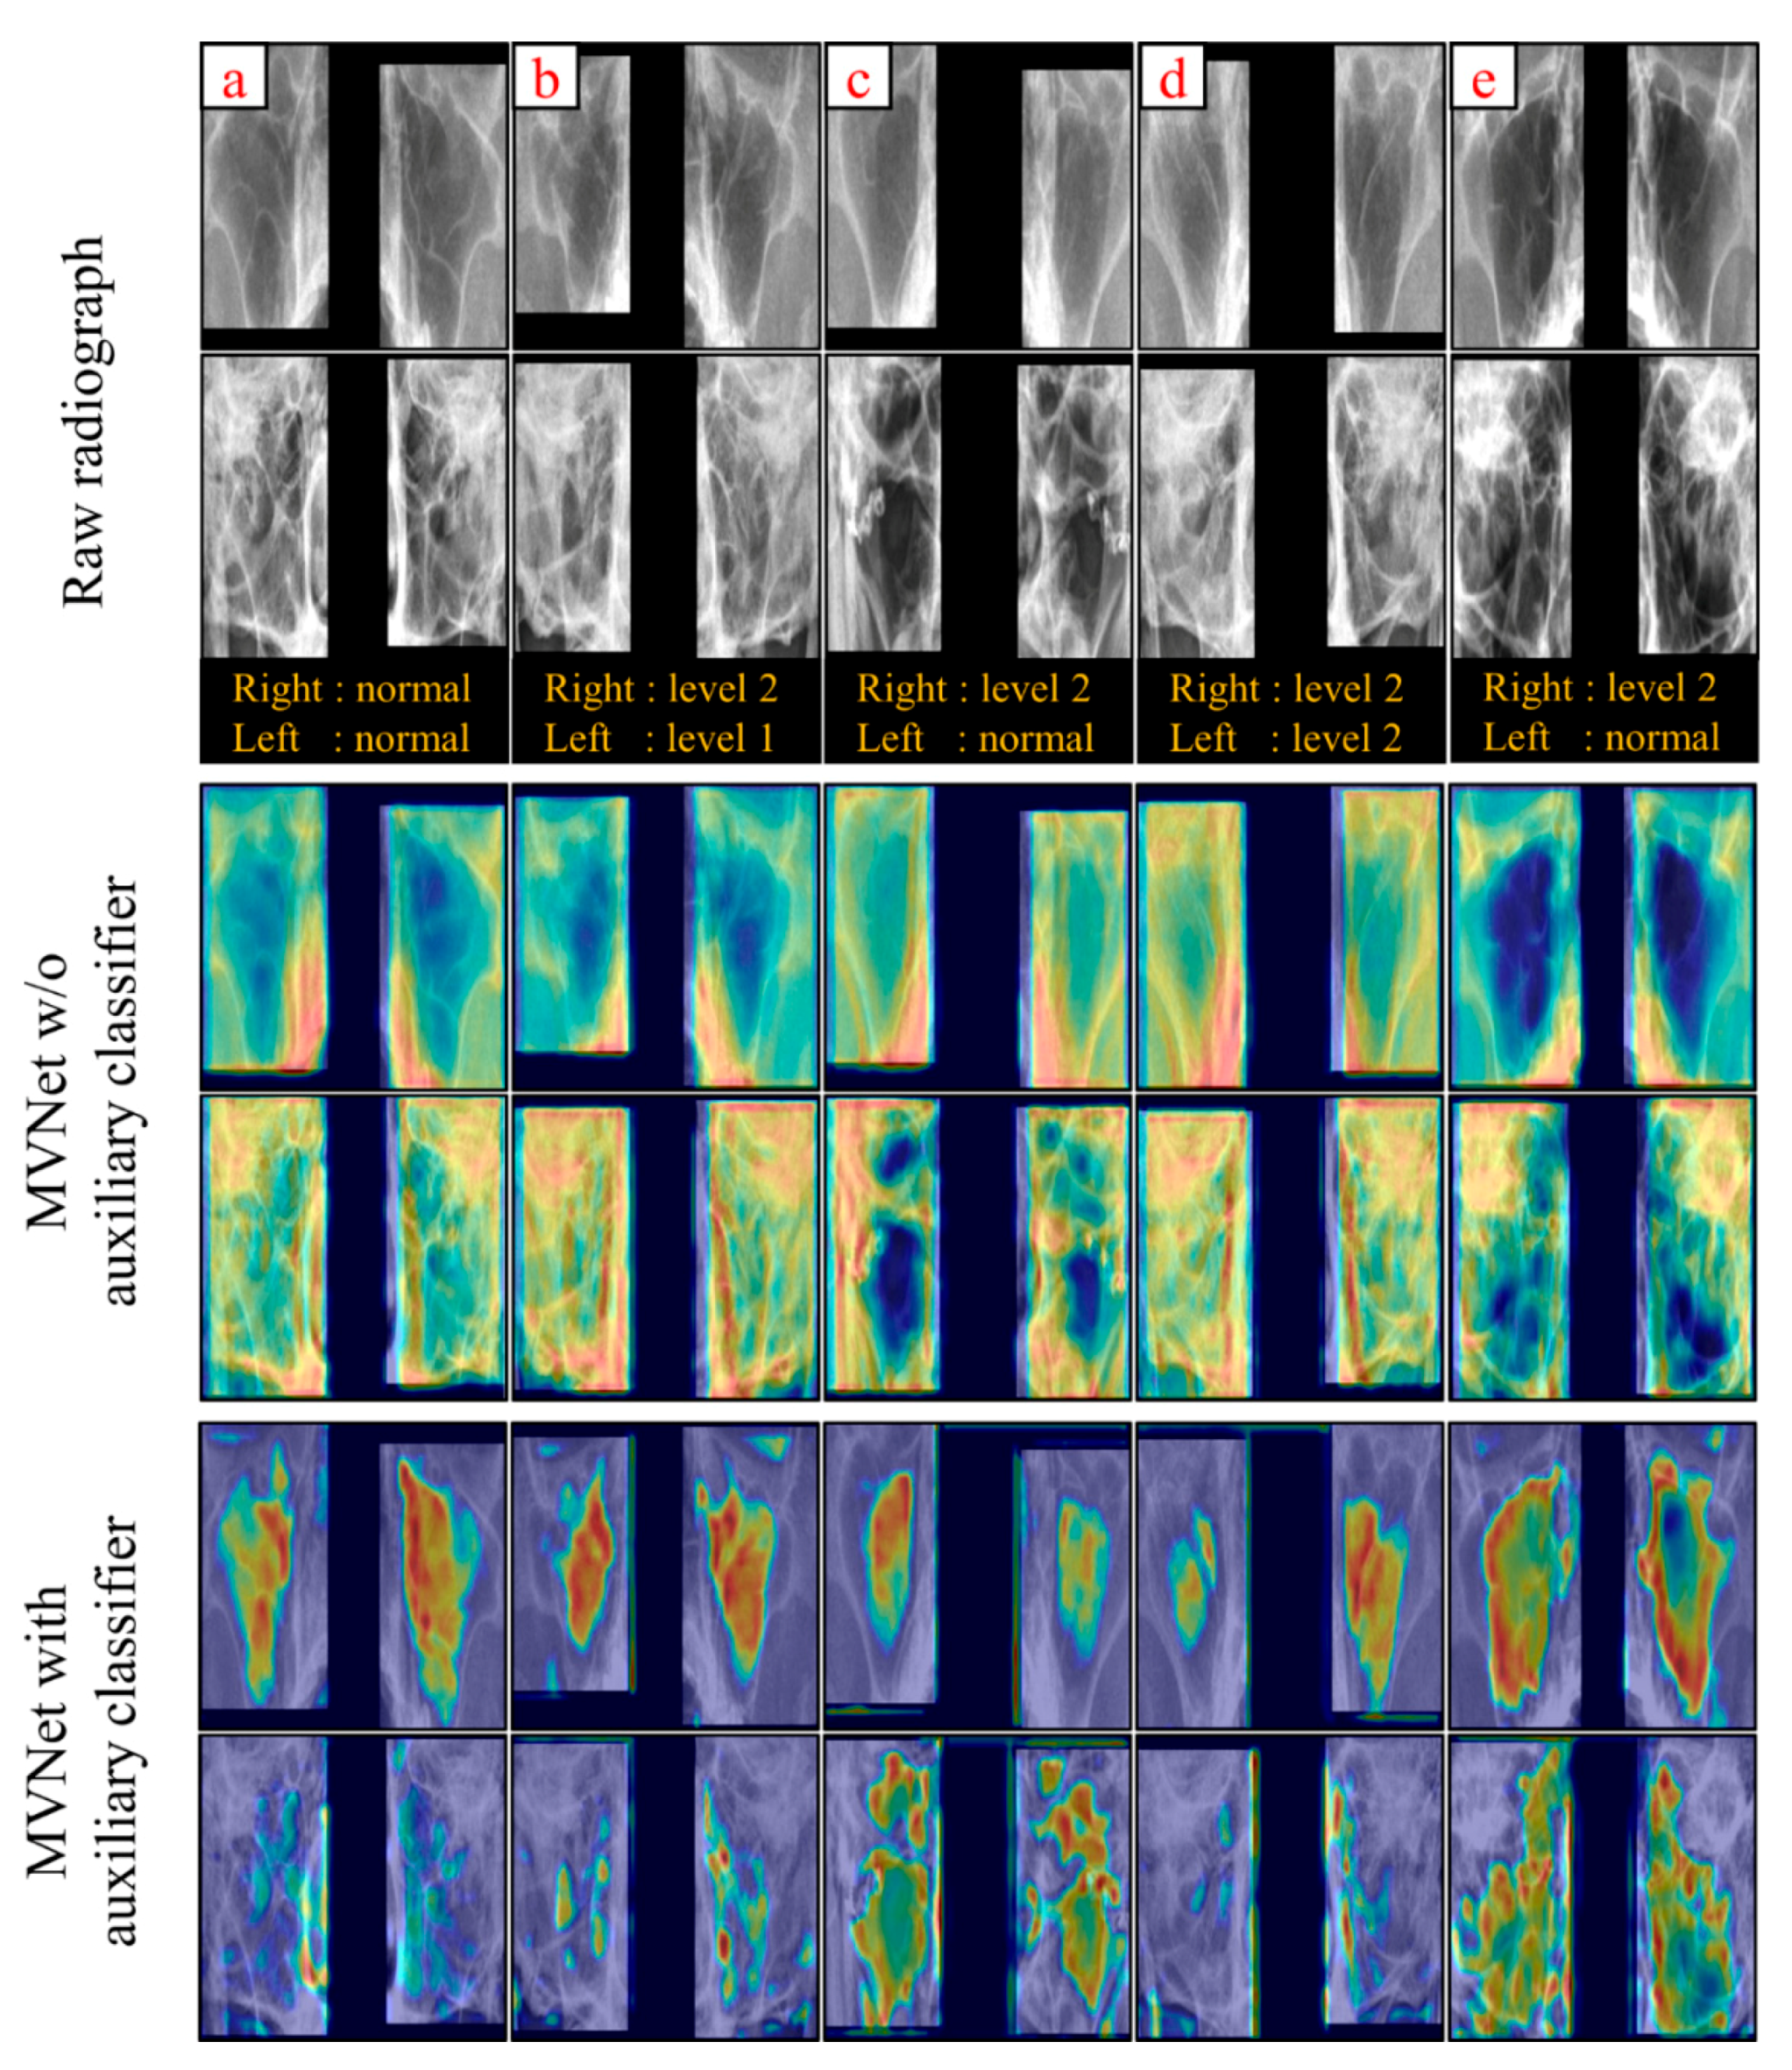

3.2. Sinusitis Classification

4. Discussion